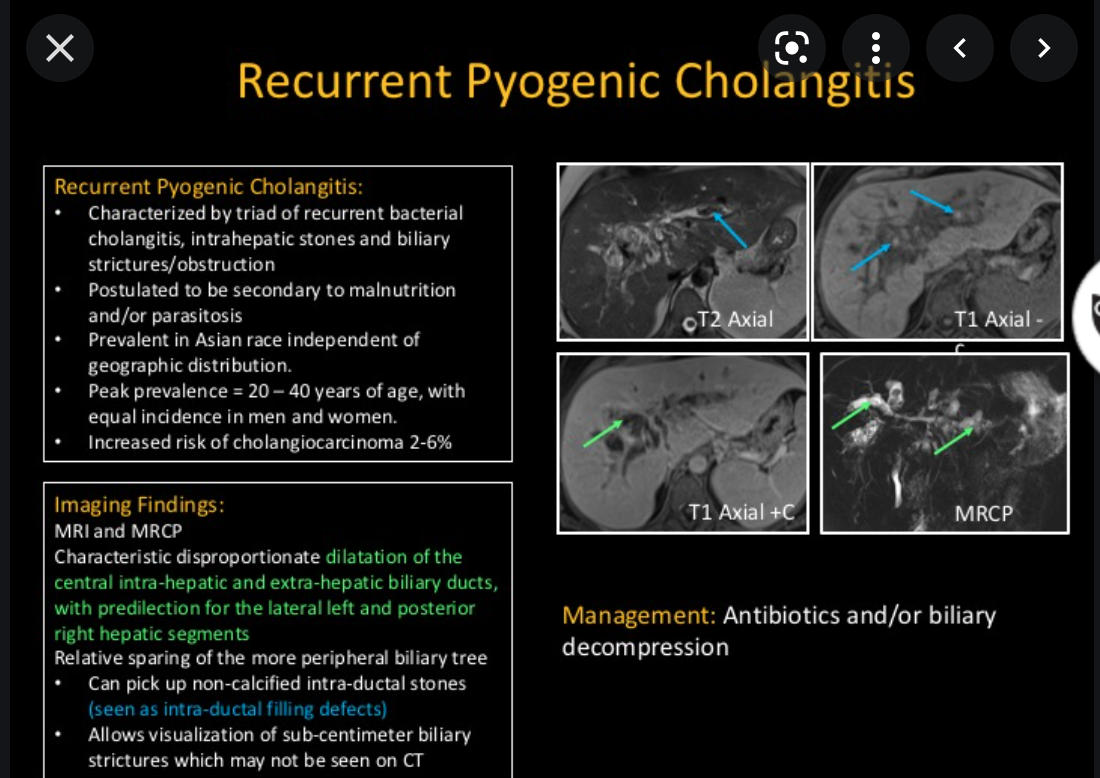

What is recurrent pyogenic cholangitis?

which lobes of the liver are most effected?

recurrent pyogenic cholangitis

- endemic disease in asia

- recurrent fever, jaundice, abdo pain

- Cuase

- Clonorchis sinensis and

- Ascaris

- bacterial super infection

- COmmon in asia, young adults

- imaging features

- Biliary dilatation

- extra and intra

- Left lobe and posterior irhgt lobe most common

- biliary strictures

- Intrahepatic calculi

- hepatolithiasis

- contains calcium biilirubinate, cellular debris and mucinous substance

- Typically hyperechoic and casts shaddows

- stones may not be sufficiatnely hyper dense to be detectable by CT

- hepatolithiasis

- Biliary dilatation

- Complications

- intrahepatic abscess formation

- hepatic atrophy as a result of PV occlusion

- Cholangioca.

- PD involvement

- GB disease in 20%